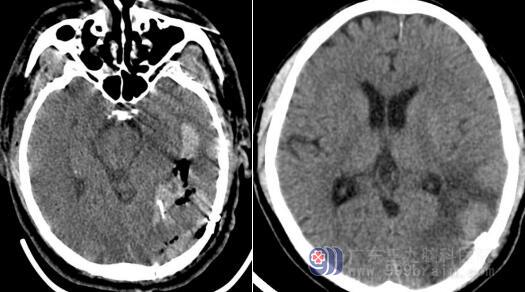

近日,张大伯突发头痛,痛感呈爆裂状,实在是忍不住了,家属带着张大伯前往当地医院就诊,CT检查显示左侧颞枕叶出血破入脑室。经过止血、降颅压、控制血压等治疗,张大伯没有明显好转,为了寻求进一步治疗前往广东三九脑科医院。

医院副院长、神经内科专家王展航接诊了张大伯,这时的张大伯已经出现意识不清。入院后立即完善相关检查,影像资料显示:左侧颞顶枕叶血肿区域显示异常。与神经外科会诊后,需紧急进行DSA造影检查以及左侧横窦区硬脑膜动静脉瘘栓塞术。医生与家属沟通并取得同意,手术过程中发现其血管畸形,在全麻下进行了“动静脉畸形切除术”+“左侧颞枕叶血肿清除术”+“硬脑膜修补术”+“颅骨成形术”,术程顺利。术后张大伯也积极配合治疗,为了能独立行走,努力做着康复······